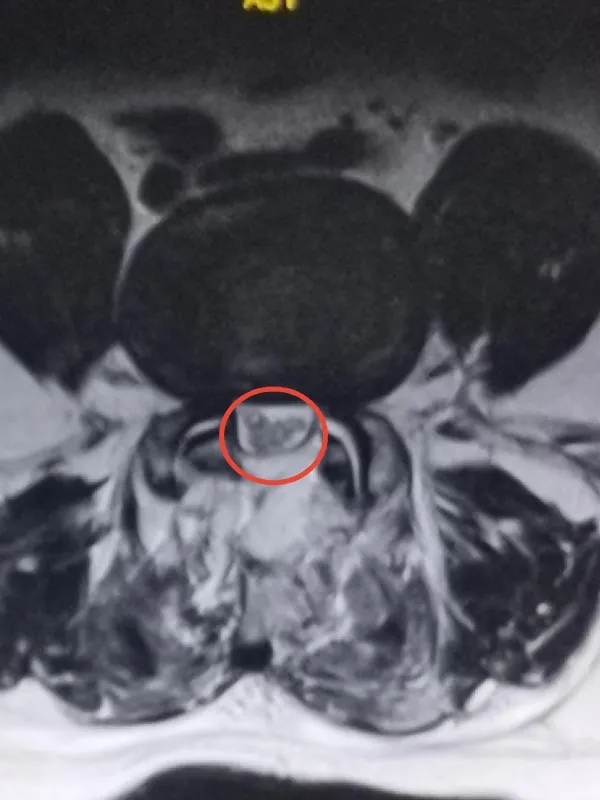

术后磁共振显示椎管狭窄改善,神经不再受压

在麻醉科和手术室的全力配合下,脊柱、骨病外科手术团队在局麻混合静脉复合麻醉下顺利完成了手术。由于王先生是双腿疼痛,双侧的神经都受到了压迫,在完成了左侧神经的解救工作后,医生巧妙地通过原切口,完成了右侧神经的解救。